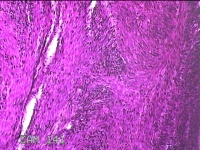

子宫肌瘤

性别

女

年龄

41岁

临床诊断

子宫肌壁间肌瘤

一般病史

发现子宫肌瘤4年余。

标本名称

大体所见

灰白色圆柱形条索状组织10.5x7x1.3㎝一堆,切面均为灰白色结节状或编织状,质硬。

图2